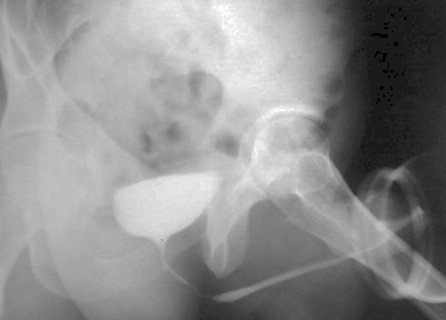

Uretrografie permicțională